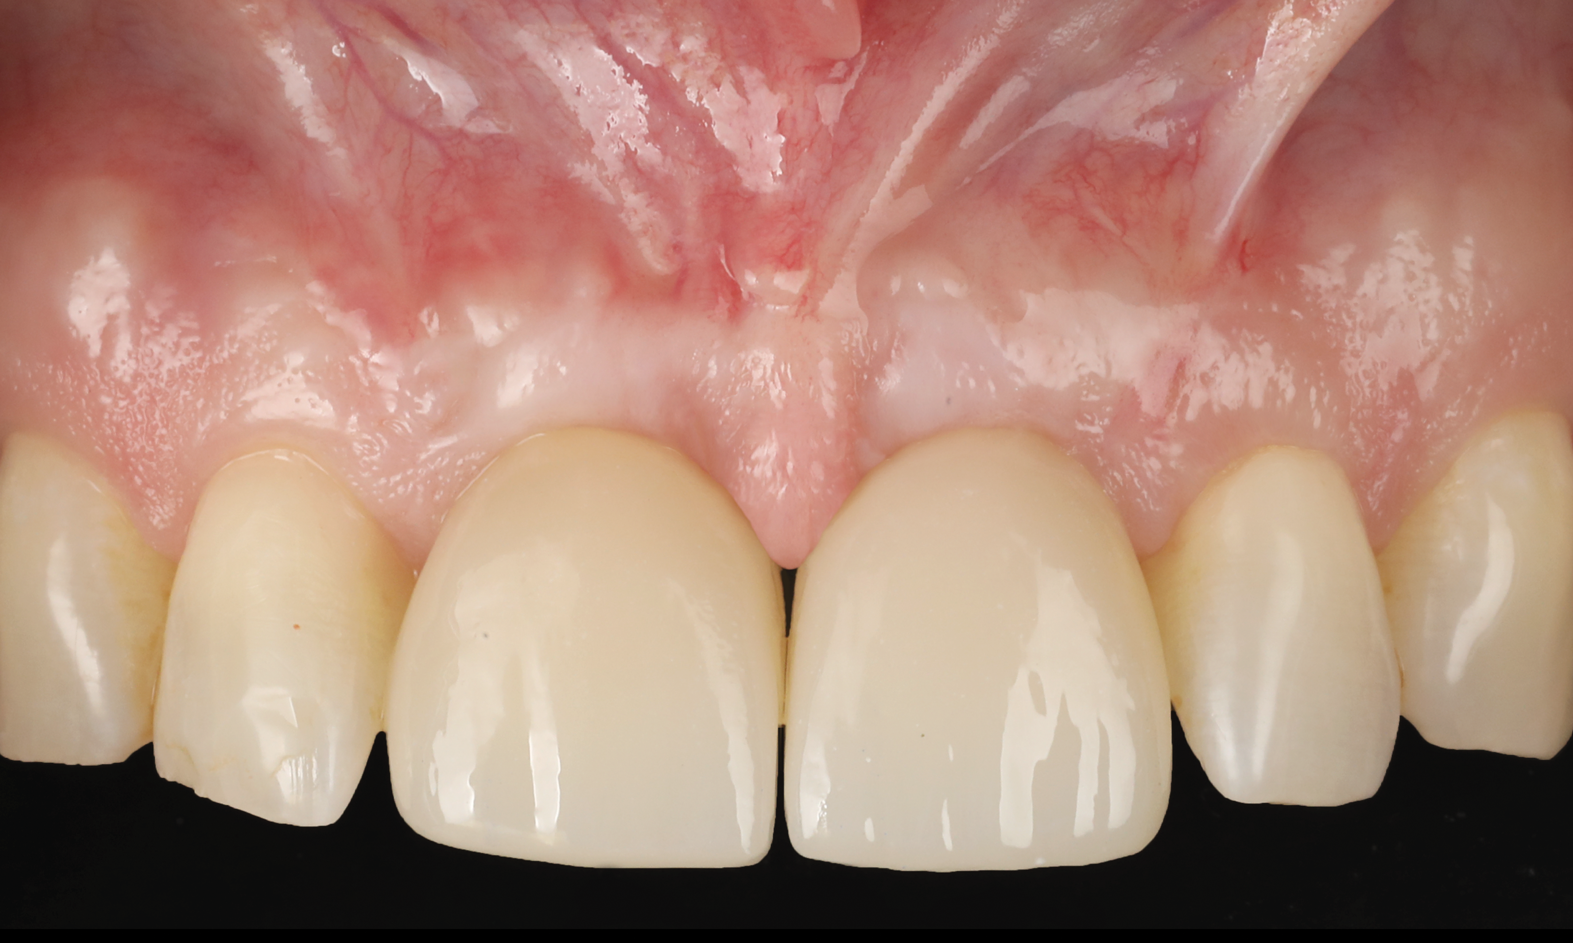

A 46-year-old systemically and periodontally healthy woman presented to the Graduate Periodontics Clinic at the University of Michigan School of Dentistry with the chief complaint of poor esthetics of her smile due to two dental implants (Nos. 8 and 9) showing their metal components (Figure 1). The patient reported that the implants had been placed 15 to 20 years previously after an accident. Clinical examination revealed that the implants had probing depths within 3 mm (facial probing depth of 3-2-3 mm for implant No. 8 and 2-2-2 mm for implant No. 9), no bleeding on probing, and no suppuration; the implants were therefore diagnosed as healthy (Figure 1 and Figure 2). The papilla between the two implants was deficient on the buccal aspect. The implants were buccally positioned, and a substantial lack of soft-tissue volume was noted.

Fig 1. Clinical view at presentation.

Figure 1

Fig 14. Final outcome at 1 year.

Figure 14

Fig 15. Clinical comparison of the volumetric gain obtained with the intervention, frontal views. Fig 15: Frontal view at baseline. Fig 16: Frontal view at 1-year post-treatment.

Figure 15

Fig 16. Clinical comparison of the volumetric gain obtained with the intervention, frontal views. Fig 15: Frontal view at baseline. Fig 16: Frontal view at 1-year post-treatment.

Figure 16